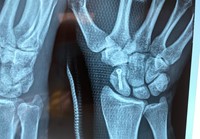

Διάγνωση Κατάγματος Σκαφοειδούς Οστού

Απεικονιστικός έλεγχος: Περιλαμβάνει προσθιοπίσθια, πλάγια και την ειδική λήψη σκαφοειδόυς (προσθιοπίσθια με το καρπό σε ωλένια απόκλιση).

Σε περιπτώσεις όπου υποπτευόμαστε κάταγμα σκαφοειδούς με αρνητικές ακτινογραφίες, εφαρμόζεται γύψινος επίδεσμος σκαφοειδούς και ο ακτινολογικός έλεγχος επαναλαμβάνεται μετά από 7-10 ημέρες.

Αν οι νέες προβολές είναι πάλι αρνητικές για κάταγμα ενώ η κλινική υποψία παραμένει η διάγνωση επιβεβαιώνεται με την αξονική ή μαγνητική τομογραφία.